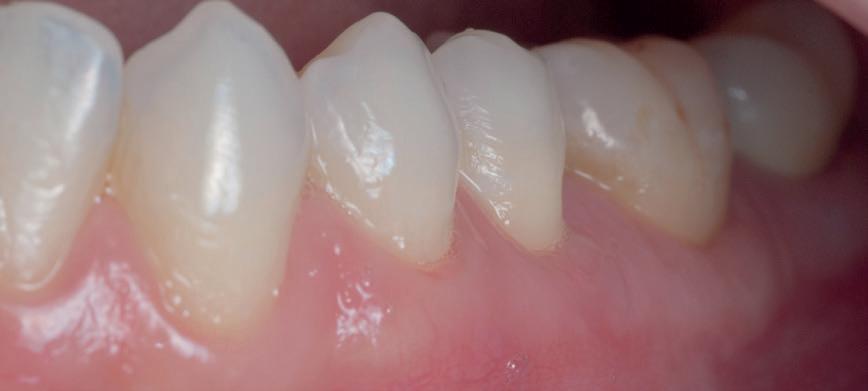

izolarea cu digă de cauciuc, restaurarea din amalgam a fost îndepărtată complet și s-a obținut accesul la cavitatea carioasă (fig. 3-5). În ciuda proximității față de țesutul pulpar, nu a avut loc nicio expunere, iar cavitatea de clasa a II-a a fost restaurată complet cu Biodentine™ (fig. 6-8).

La controlul de două luni, nu au fost raportate simptome, nu s-a obiectivat radiologic nicio leziune periapicală, iar examenul clinic a

demonstrat o vitalitate în limite normale (fig. 9-10). Prin urmare, s-a decis efectuarea restaurării definitive, păstrând Biodentine™ ca bază definitivă.

10. Restaurarea Biodentine™ după 2 luni.